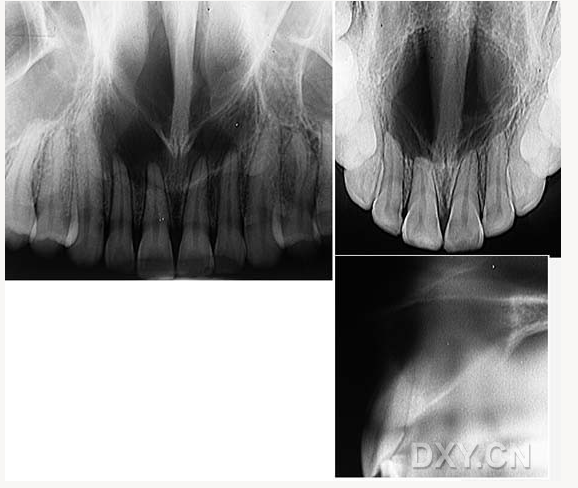

鼻鄂囊腫

根尖囊腫

鼻腭囊腫